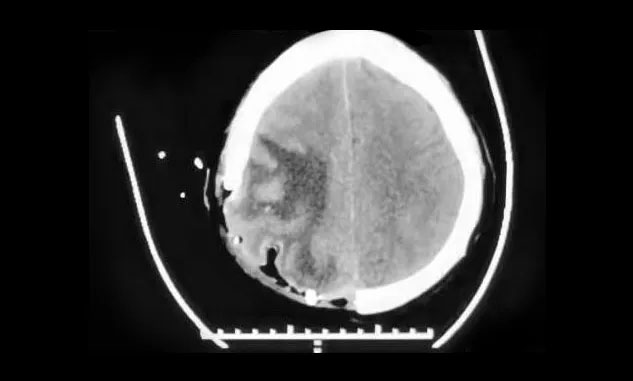

術(shù)后,患者沒有出現(xiàn)肢體運動障礙,頭暈、頭痛及嘔吐消失,目前正在康復(fù)中。下一步,明確病理結(jié)果后,將繼續(xù)MDT團隊討論,確定治療方案。

▲ 術(shù)后,中線結(jié)構(gòu)恢復(fù)正常